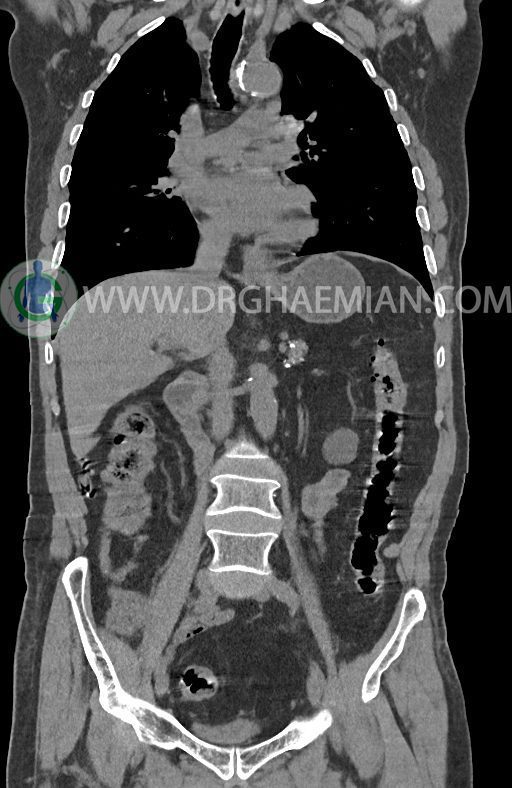

در سی تی اسکن اسپیرال ریه ها و مدیاستن، شکم و لگن با و بدون کنتراست وریدی (مولتی دیدکتور 16 با مقاطع ظریف و بازسازی کرونال) :

–لنف نودهای مدیاستن با SAD ≤ 9 mm

–افزایش ضخامت تومورال دیستال مری و GEJ در سگمانی به طول 4cm-5cm (T2 or T3)

-3 لنف نود رژیونال با SAD ≤ 9 mm دیده می شود. (N2)

–آتروفی نسبی پانکراس همراه با فوکوس های کلسیفیه ی منتشر پارانشیم مطرح کننده ی پانکراتیت مزمن

-CBD بسیار دیلاته (16mm) همراه با دیلاتاسیون مجاری داخل کبدی سنترال بدون شواهد سنگ یا توده در مسیر

–کیست های کورتیکال متعدد هر دو کلیه به بزرگترین قطر 56mm

–پروستات به دیامتر عرضی بزرگ حاوی فوکوس کلسیفیه

نتیجه : T(2or3)/N2/M0